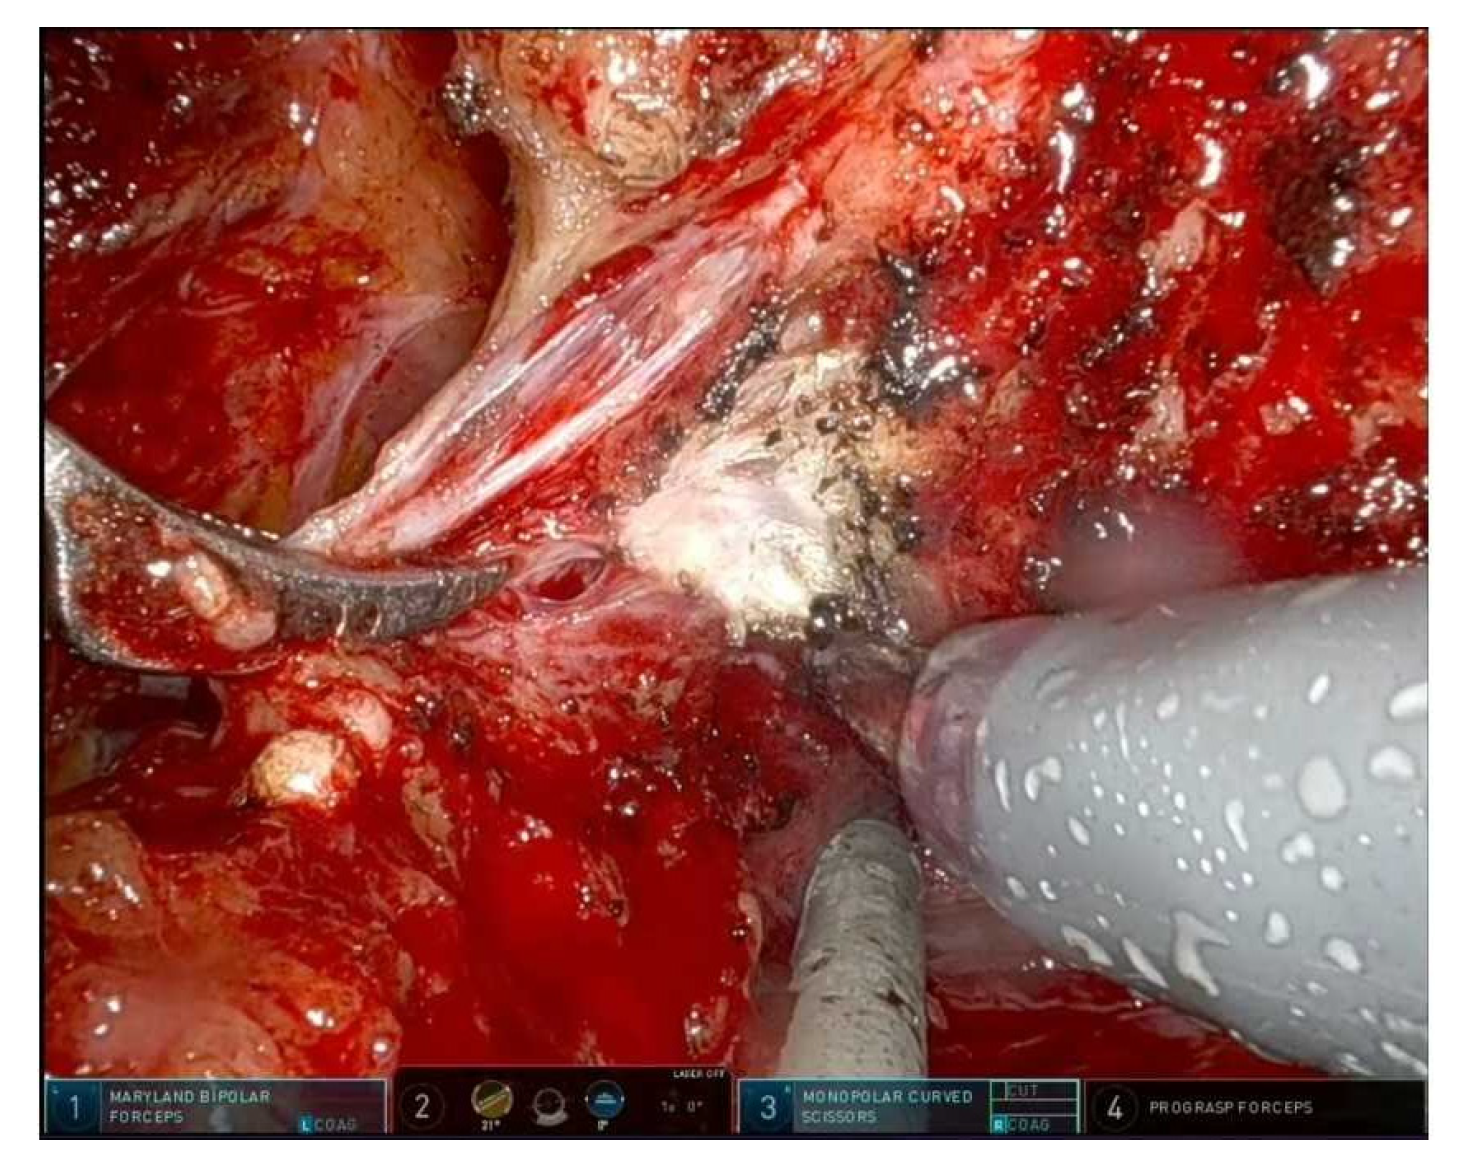

- Intrafascial: maximal preservation, suitable for low-risk disease with favorable anatomy; Figure 2 shows an intrafascial dissection phase;

Figure 2. Clipless right prostate pedicle section and develop of right intrafascial plane. - Interfascial: partial preservation, balances functional and oncological outcomes; Figure 3 shows a frame during interfascial dissection;